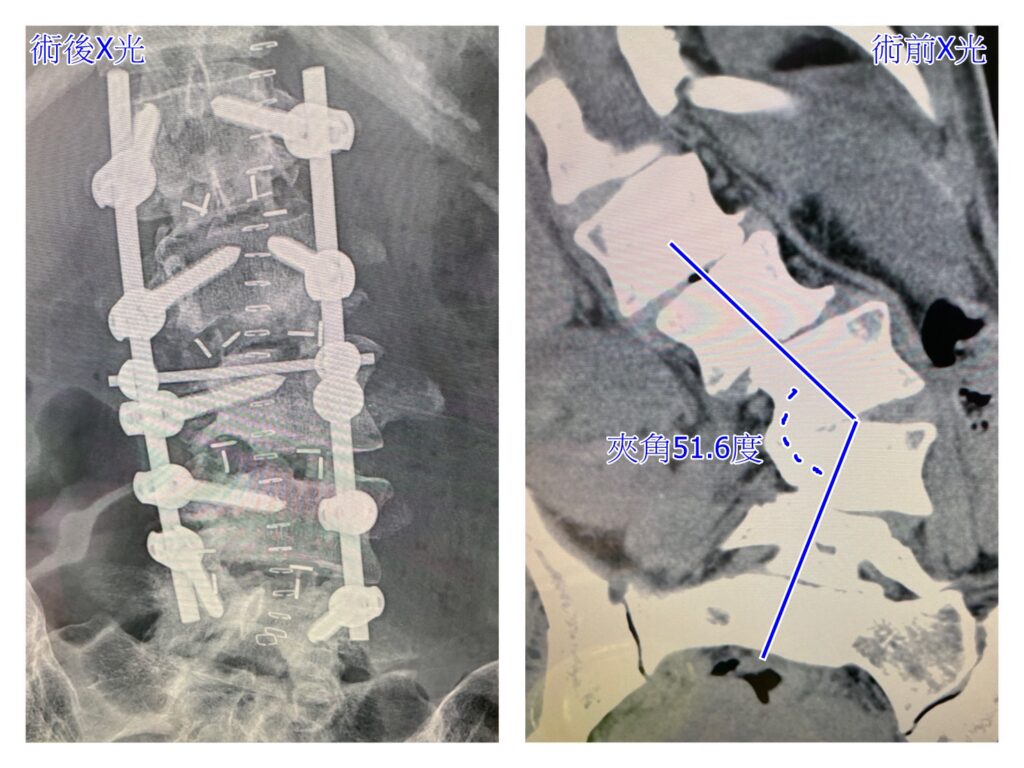

<figure class="wp-block-image size-large"><img loading="lazy" decoding="async" width="1024" height="740" src="https://wellnews.media/wp-content/uploads/2023/03/gout-2-1024x740.jpg" alt="" class="wp-image-6760" srcset="https://wellnews.media/wp-content/uploads/2023/03/gout-2-1024x740.jpg 1024w, https://wellnews.media/wp-content/uploads/2023/03/gout-2-300x217.jpg 300w, https://wellnews.media/wp-content/uploads/2023/03/gout-2-768x555.jpg 768w, https://wellnews.media/wp-content/uploads/2023/03/gout-2-1536x1110.jpg 1536w, https://wellnews.media/wp-content/uploads/2023/03/gout-2-2048x1480.jpg 2048w, https://wellnews.media/wp-content/uploads/2023/03/gout-2-324x235.jpg 324w, https://wellnews.media/wp-content/uploads/2023/03/gout-2-696x503.jpg 696w, https://wellnews.media/wp-content/uploads/2023/03/gout-2-1068x772.jpg 1068w, https://wellnews.media/wp-content/uploads/2023/03/gout-2-581x420.jpg 581w, https://wellnews.media/wp-content/uploads/2023/03/gout-2-1920x1387.jpg 1920w" sizes="(max-width: 1024px) 100vw, 1024px" /><figcaption class="wp-element-caption"><strong>痛風患者手部X光片，紅圈為痛風石，黃色箭頭為遭破壞骨頭。(圖/花蓮慈濟醫院堤供)</strong></figcaption></figure>